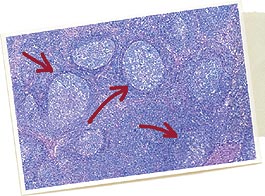

2. Présence de lésions microscopiques caractéristiques dans les organes lymphoïdes : le rapport d’histologie du laboratoire d’analyses mentionne alors une déplétion lymphocytaire avec infiltration histiocytaire (granulomateuse). Il y a une présence variable de cellules géantes multinucléées (au milieu des années 90, ce critère était considéré comme essentiel ; depuis, il n’est que secondaire). La présence d’inclusions intracytoplasmiques est fréquente (si une technique additionnelle est mise en œuvre, il est possible d’observer que ces agrégats contiennent du PCV2).

3. Détection de PCV2 dans les lésions des tissus lymphoïdes typiques (point 2), chez cet animal (point 1), par une technique qui permet d’estimer la quantité de PCV2 (ses protéines, par immunomarquage, ou son génome, par hybridation in situ), et de l’associer à l’intensité des lésions.

Ce diagnostic individuel doit donc faire appel au laboratoire d’analyses. Plusieurs organes lymphoïdes peuvent être prélevés car les lésions de MAP se retrouvent dans l’ensemble de ce système : ganglions mésentériques, amygdales…